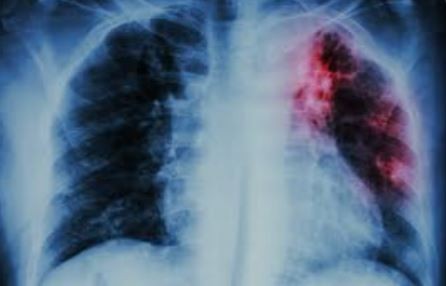

Las autoridades sanitarias de Mar del Plata confirmaron un caso de tuberculosis en un adolescente que asiste a un colegio de la ciudad y activaron de inmediato el protocolo de prevención y seguimiento para evitar posibles contagios.

El diagnóstico fue ratificado por la Zona Sanitaria VIII, la Secretaría de Salud de General Pueyrredón y el Colegio Galileo Galilei, donde el alumno cursa sexto año. Se trata de una enfermedad infecciosa que se transmite por vía aérea, lo que motivó la implementación de medidas preventivas en el entorno cercano del paciente.